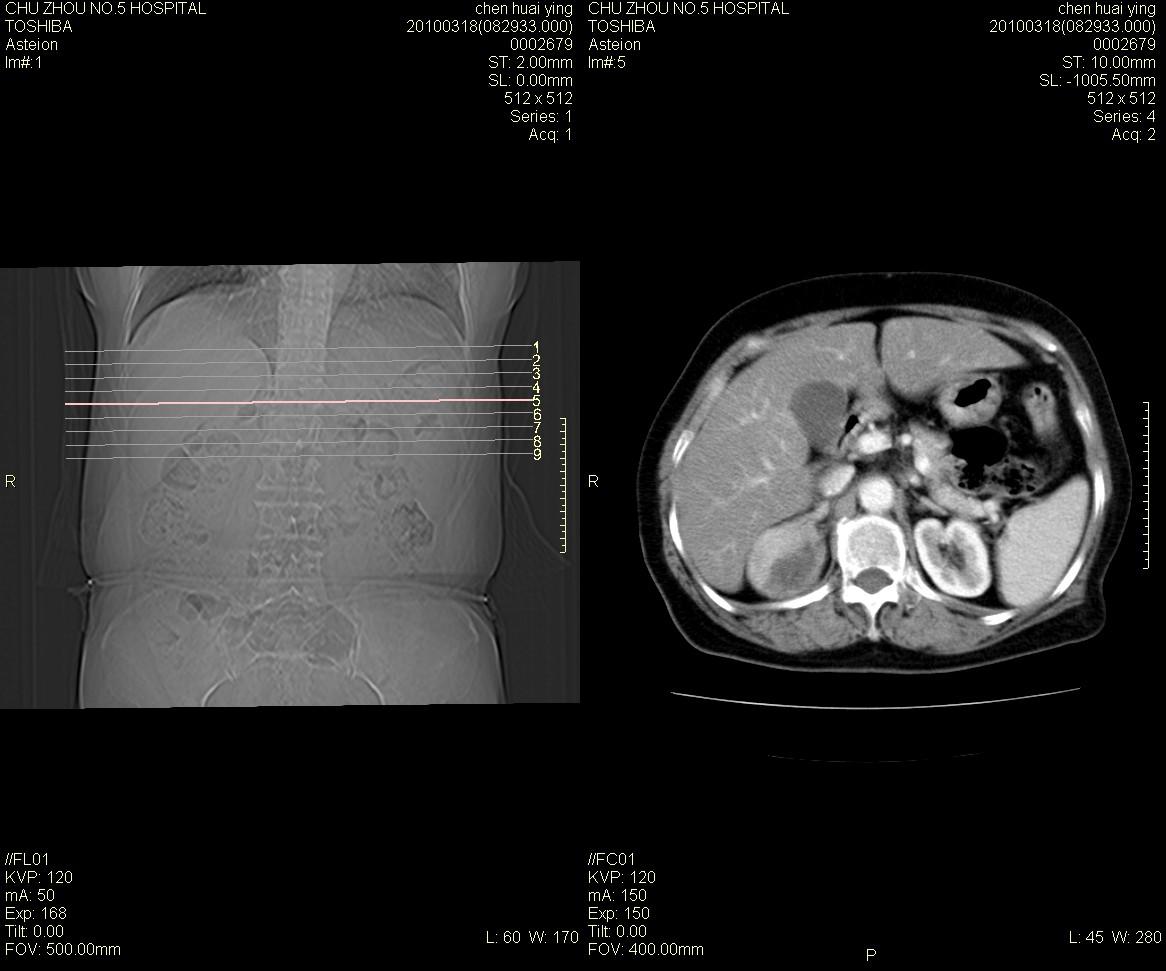

标题: CT25148 肾上腺增强

ct25148增强图片

动脉期太早了,扫的有点低。考虑良性占位右侧肾上腺嗜铬细胞瘤并坏死囊变可能性大,神经鞘瘤不排除。

右侧肾上腺占位性病变,病人是否有高血压?嗜铬细胞瘤?

右侧肾上腺嗜铬细胞瘤并坏死囊变可能性大